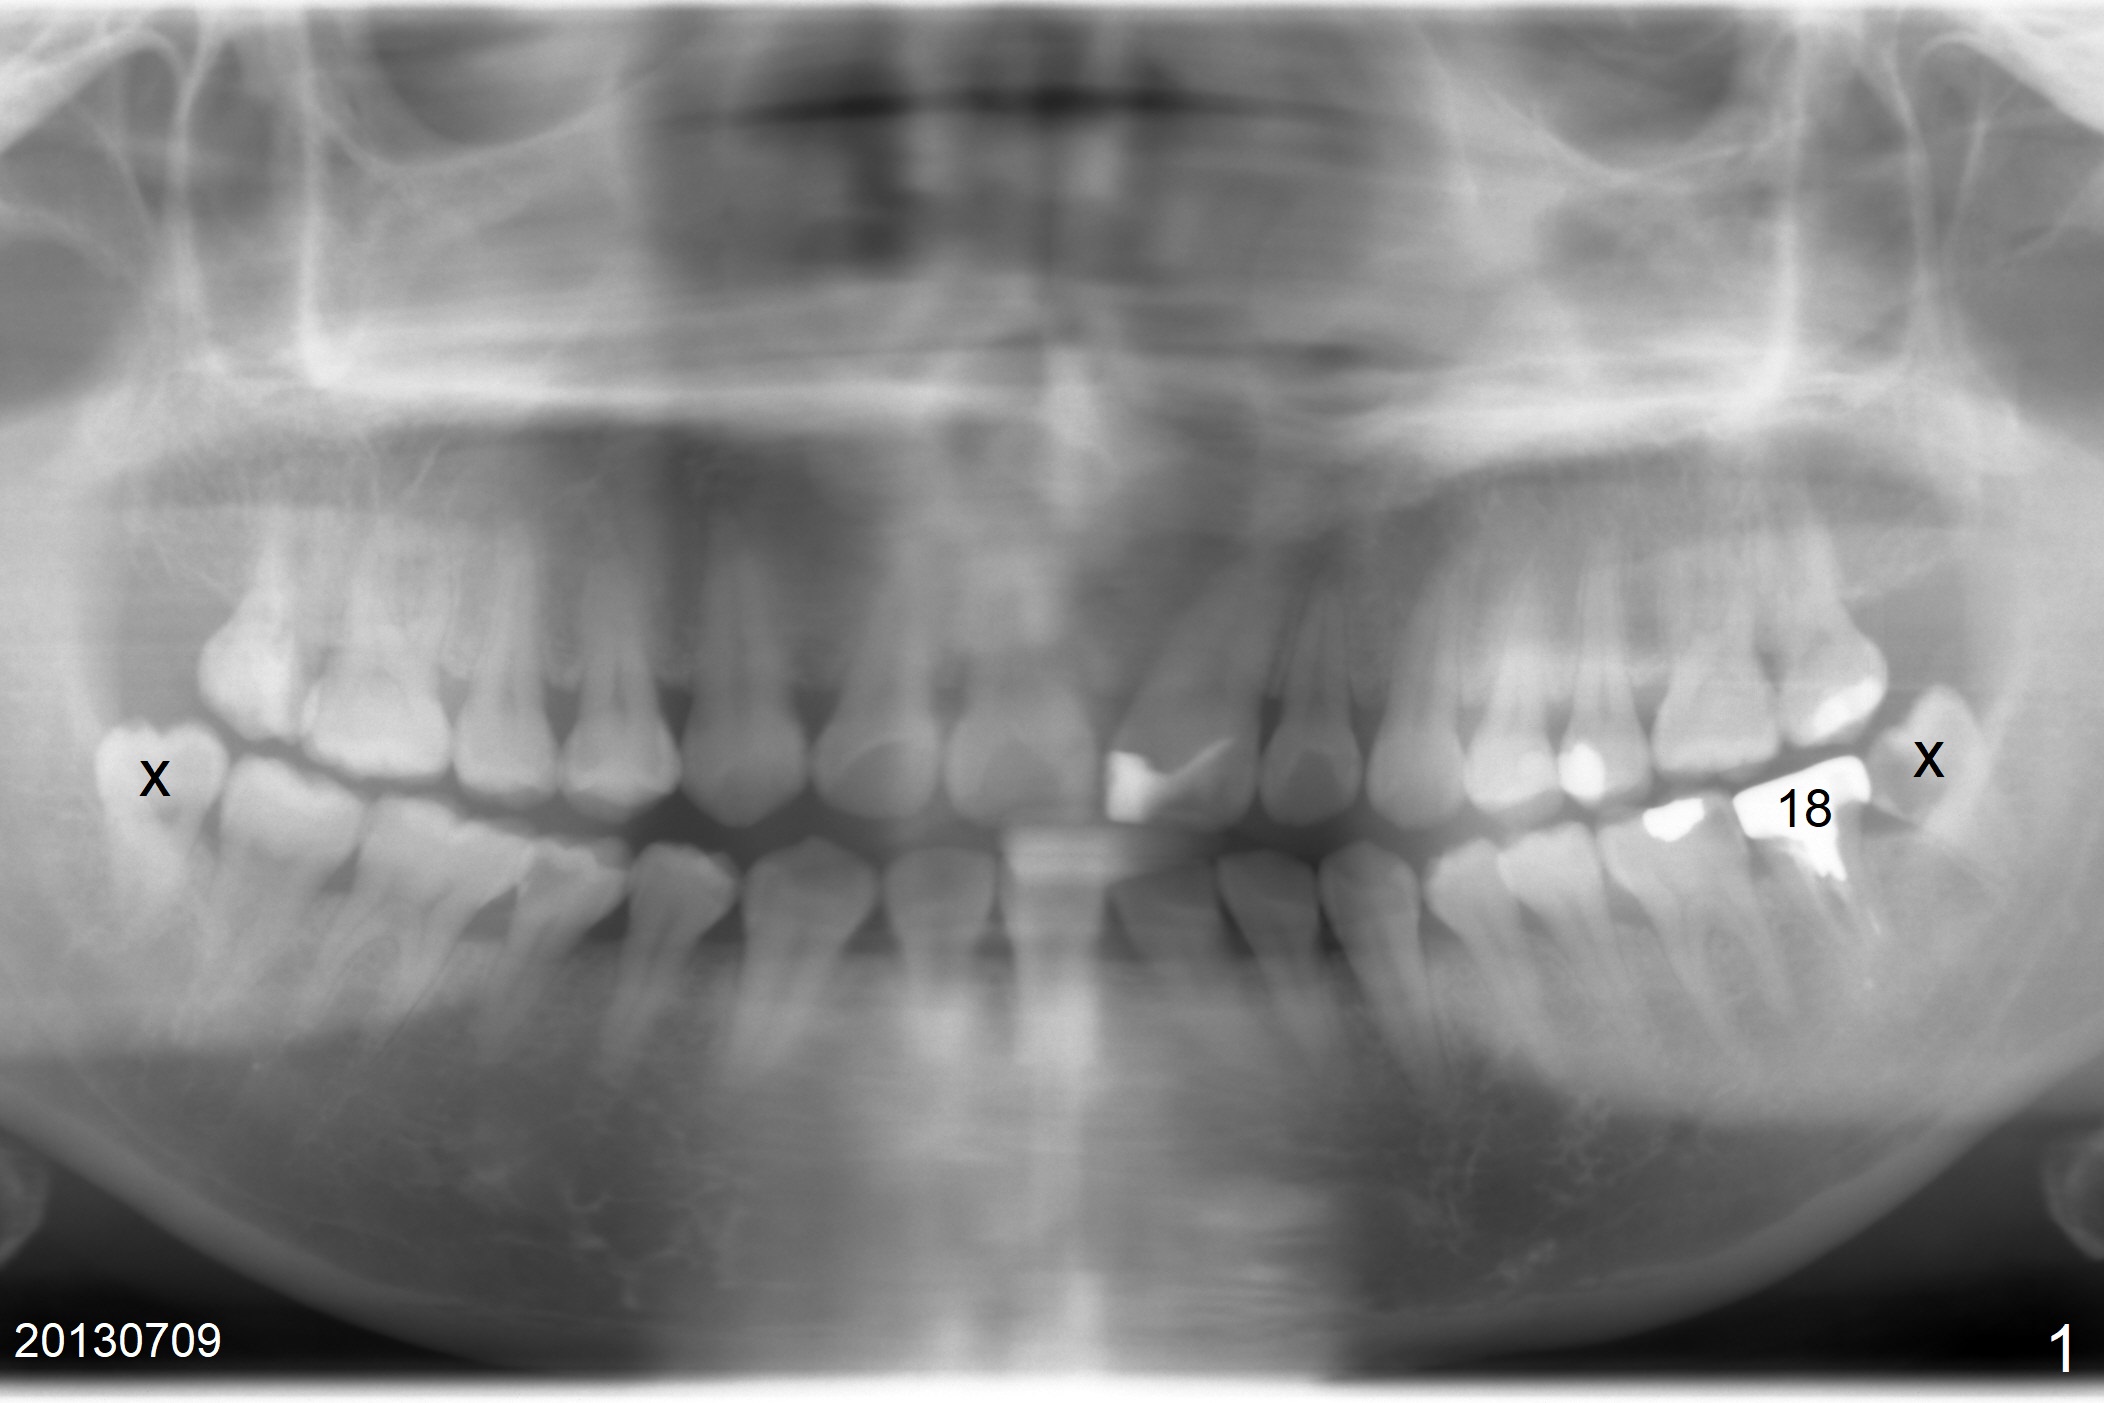

A 34-year-old woman has been our patient for >5 years. Since then, the teeth #17 and 32 have been extracted (Fig.1 x). The main issue is the metal crown at #18, which had occlusal perforation. The crown was recemented once. The mesiolingual margin is wide and subgingival. After redo, the Zirconia crown fractured once and finally dislodged (Fig.3), partially due to #15 supraeruption (Fig.2 arrow, trimmed during crown redo). Following extraction, use starter drill and 2 mm drill with 8 mm stopper to initiate osteotomy in the mesial slope of the socket (Fig.3 yellow line). The stopper should stop prematurely in the mesiocoronal aspect of the mesial slope, the depth should be a little longer than 5.6 mm (Fig.3 pink line). Insert a marked parallel pin for X-ray depth confirmation. Considering the opposing tooth supraeruption, a probably 5x10 mm SM implant will be placed deep with a cemented abutment with 1 mm cuff. But at first a temporary abutment will be used most likely. Make a provisional as wide as possible apically so that it is easy to take impression later on.